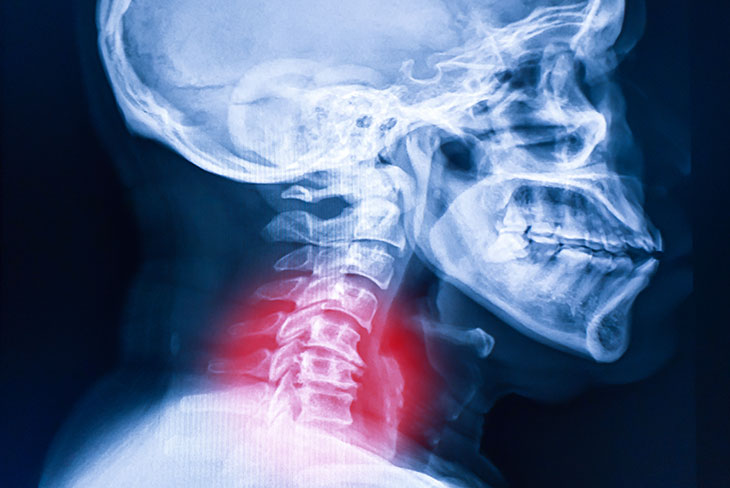

A whiplash injury from a California car accident is a soft tissue injury to the neck, caused by a rapid, forceful back-and-forth movement.

However, securing fair compensation remains challenging. Insurance companies frequently question the severity of whiplash because it doesn’t appear on an X-ray, and symptoms are delayed. Proving your injury requires consistent medical documentation and a clear understanding of the claims process.

When another car hits yours, especially from behind, your head snaps back and then forward with incredible force. This motion stretches and tears the soft tissues, commonly known as the muscles and ligaments, in your neck. Think of it like a rubber band being stretched too far, too fast. Those tissues are not designed for that kind of abrupt movement, and the resulting damage is what we call whiplash.

Why You Must Take These Claims Seriously from Day One

Because whiplash is an “invisible injury”, one that doesn’t show up on an X-ray, it is one of the most frequently challenged claims. The insurance company for the at-fault driver is a business, which means it must balance paying claims with protecting its financial interests. Their investigation will look for any reason to argue that your claim is worth less than you believe.